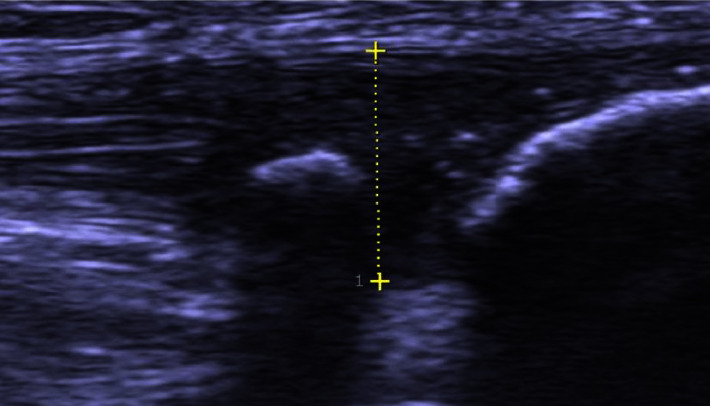

Methods: The study included 344 consecutive patients (306 males, mean age 27 years, range 17-58; 38 females, mean age 24 years, range 18-44) from 21 different countries seeking help for therapy-resistant jumper's knee. There were 274 elite athletes, 168 being full-time professionals. All were diagnosed to have tendinopathy in the proximal patellar tendon and were operated on with ultrasound- and Doppler-guided arthroscopic shaving surgery.

Abstract Image